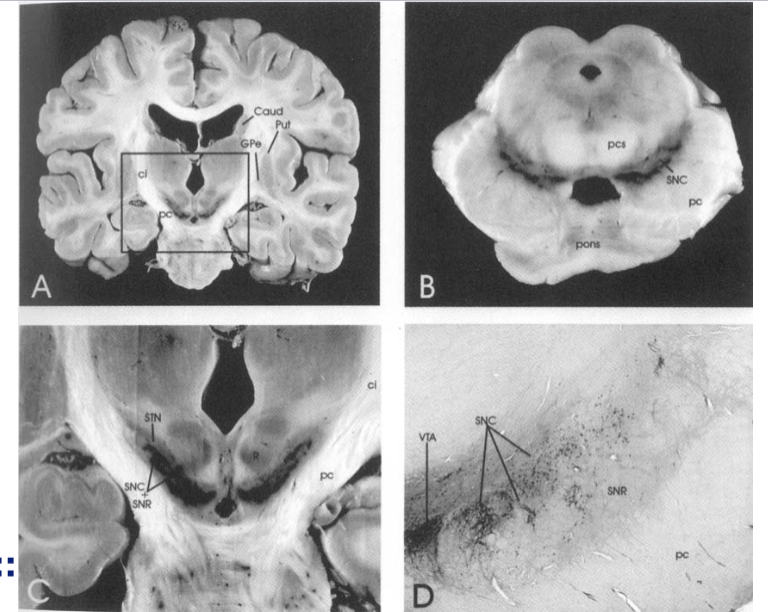

Striatum= laterale zijde van het laterale ventrikel

capsula interna klieft het striatum in 2 delen–> nucleus caudatus mediaal en putamen lateraal

nucleus accubens verbind striatum onderin (beloningscentrum)

globus pallidus bestaat uit pars interna en externa

nucleus subthalamicus is een lensvormige structuur en ligt onder de thalamus

substantia nicra ligt tussen de nucleus ruber en de pedunculus cerebri

Ligt aan de binnenkant van de pedunculus cerebri en bestaat uit 2 delen:

pars compacta (SNC)–> exctaitoir

pars reticulata (SNR)–> inhibitoir

beide onderdelen verzorgen de output van de basale kernen. De input komt van de cortex cerebri.